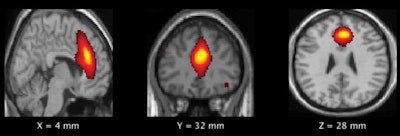

The players also underwent functional MRI (fMRI) scans before and after the season to detect changes in spectral power in the brain's default mode network. The network includes structures that activate when a person is awake and engaged in introspection or the processing of emotions. Previous studies have shown that the spectral power of resting-state networks typically decreases as a person becomes older. Such declines are indicative of normal gray-matter pruning.

Their theory proved accurate, as the frontal default mode network demonstrated a significant increase in spectral power in the high-impact group (p = 0.00018), compared with results from the low-impact players. There was also a statistically significant increase in gray-matter volume in the same frontal regions of the default mode network for the high-impact group (p = 0.005).